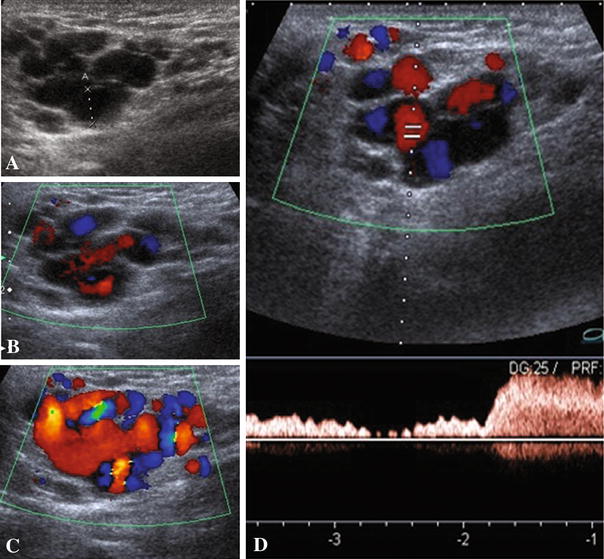

Round ligament varicosities show a venous flow waveform demonstrated... Download Scientific Round Ligament Varicosities Round ligament varicosities associated with uterine varicosities are rare during pregnancy. Round ligament varicosities are dilated and tortuous veins in the round ligament, these are rare although most commonly seen. Round ligament varicosities (rlvs) are rare, and only occur in pregnancy. We report the case of a. Round ligament varicosities occur almost exclusively in pregnant and postpartum women and present. Round Ligament Varicosities.